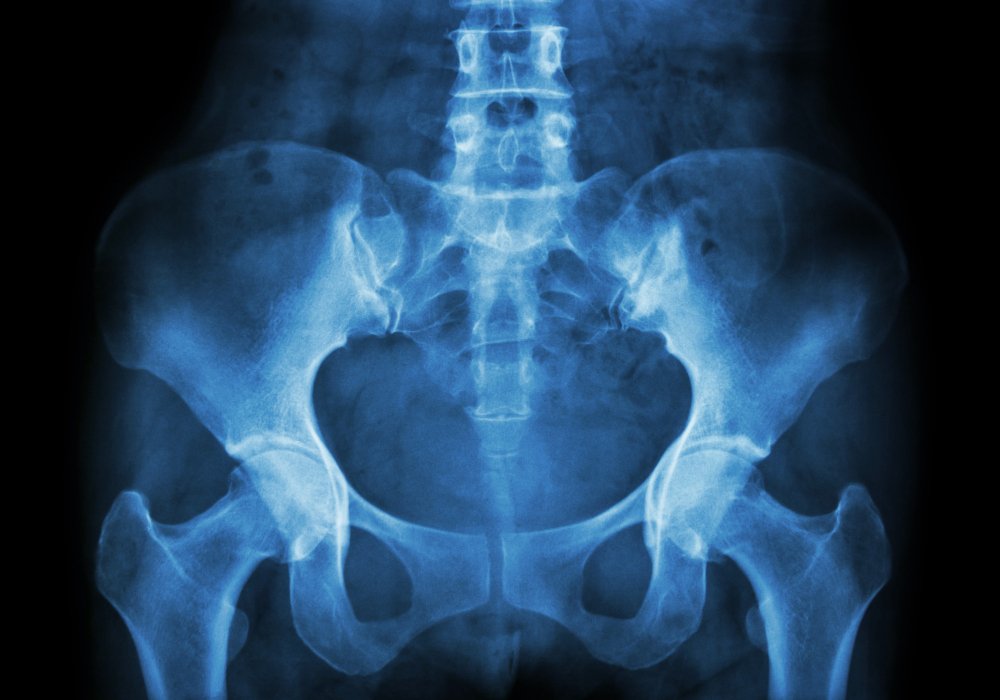

Notre équipe propose une imagerie numérique de haute définition pour le bassin, la hanche et les articulations sacro-iliaques. Les clichés comprennent des incidences face, profil, 3/4 et des prises dynamiques adaptées à votre clinique.

Nous visons un diagnostic précis dès le premier passage. Grâce à un plateau technique fiable, nos radiologues mesurent les axes et interlignes pour fournir des comptes rendus exploitables par votre médecin ou chirurgien.

La radiologie met en évidence fractures, signes d’usure (pincement, ostéophytes) et conflits fémoro-acétabulaire.

- Nous précisons les clichés standards : bassin de face, incidences ciblées et hanches en 3/4.

Le technicien installe et positionne en face puis en profil selon l’indication. Nous réalisons des incidences ciblées des articulations sacro-iliaques pour une imagerie précise.

La radiologie numérique couvre les examens standards : bassin, hanche, sacro‑iliaques, rachis en téléradiographie, thorax et abdomen sans préparation.

Qualité d’image et mesures pour un diagnostic fiable

Nos outils améliorent la finesse des détails osseux et la reproductibilité des mesures. Cela aide au suivi post‑opératoire et à la décision thérapeutique.

| Radiologie numérique | Contours articulaires nets, mesures fiables | Sur site |